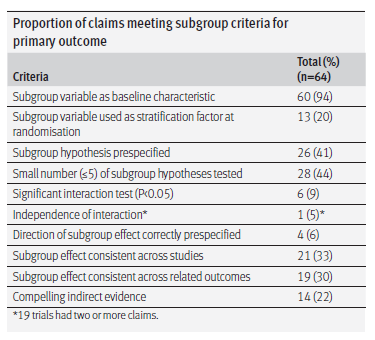

е…ідәҺдәҡз»„еү–жһҗж•Ҳжһңзҡ„еҸҜйқ жҖ§����пјҢеӣӣе·қеӨ§еӯҰеӯҷй‘«ж•ҷжҺҲеӣўйҳҹжҸҗеҮәдәҶ9дёӘж ҮеҮҶд»ҘдҫӣеҸӮиҖғпјҲеӣҫ2пјү[10]��гҖӮAENEASе’ҢFURLONGе°Ҷи„‘иҪ¬з§»дҪңдёәйў„и®ҫеҲҶеұӮеӣ зҙ ����пјҢAENEASдёӯи„‘иҪ¬з§»жӮЈиҖ…еңЁйҳҝзҫҺжӣҝе°је’ҢжҜ”з…§з»„зҡ„жј«иЎҚе°ӨдёәдёҖиҮҙпјҲ26.2% vs 27.4%пјү����пјҢдҪҶеңЁдәҡз»„ж•Ҳжһңзҡ„еҸҜйҮҚеӨҚжҖ§дёҠ����пјҢйҳҝзҫҺжӣҝе°је’ҢдјҸзҫҺжӣҝе°јеқҮе°ҡж— е…¶д»–йҡҸжңәжҜ”з…§IIIжңҹдёҙеәҠз ”з©¶ж•ҲжһңжҸӯжҷ“����пјҢе°ҡжңүеҫ…иҝӣдёҖжӯҘйӘҢиҜҒ��гҖӮFLAURAеҲҷжңүAURA3з ”з©¶[11]еҸҜдҫӣеҸӮиҖғ����пјҢдёӨиҖ…еңЁи„‘иҪ¬з§»дәҡз»„дёӯеү–жһҗж•ҲжһңеқҡжҢҒдёҖиҮҙ����пјҢиҷҪ然дёӨйЎ№з ”з©¶д»ҚдҝқеӯҳдёҖе®ҡе·®еҲ«����пјҢдёҖдёӘжҳҜдёҖзәҝз ”з©¶����пјҢдёҖдёӘжҳҜдәҢзәҝз ”з©¶����пјҢдёҖе®ҡж°ҙе№ідёҠд»ҚжңүеҠ©дәҺжҸҗй«ҳеҘҘеёҢжӣҝе°јдәҡз»„еү–жһҗж•Ҳжһңзҡ„еҸҜдҝЎеәҰ����пјҢдҪҶFLAURA并жңӘе°Ҷи„‘иҪ¬з§»дҪңдёәйў„и®ҫеҲҶеұӮеӣ зҙ ����пјҢеҜјиҮҙFLAURAдёӯеҘҘеёҢжӣҝе°је’ҢжҜ”з…§з»„зҡ„и„‘иҪ¬з§»жӮЈиҖ…еҹәзәҝе№іиЎЎдёҚеҰӮAENEASпјҲ19% vs 23%пјү����пјҢеҗҢж—¶еҹәзәҝдјҙи„‘иҪ¬жӮЈиҖ…еҚ жҜ”д№ҹдҪҺдәҺ AENEASе’Ң FURLONG��гҖӮ

еӣҫ2. еҲӨж–ӯдәҡз»„еү–жһҗж•ҲжһңеҸҜйқ жҖ§зҡ„еҸӮиҖғж ҮеҮҶ